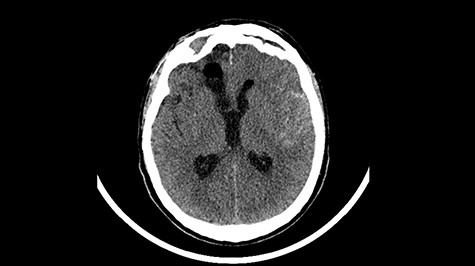

Head CT after polypectomy—seen defects of the upper left orbital wall. (Department of Neurosurgery own material).

In described case, a head CT scan after polypectomy confirmed the subarachnoid hemorrhage (Fig. 1). In addition, the presence of air in the ventricular system was visible, and presence of defects of the upper left orbital wall and ethmoid on both sides (Fig. 3). In the CT scan sphenoid sinus, frontal and ethmoidal sinuses on both sides and right maxillary sinus airless, filled with blood and soft tissue. The changes also concerned the lateral part of the left maxillary sinus (Fig. 4).

The present bone defects were most probably caused by the development of osteomalytic foci as a consequence of the spread of the inflammatory process within the diploe of flat skeletal skull bones, in the course of chronic rhinosinusitis. Both underestimating the severity of complaints in the course of chronic rhinosinusitis and delaying the implementation of surgical treatment led to massive bone destruction, which had an impact on the development of further complications after polypectomy (including subarachnoid hemorrhage). Performed angio-CT excluded any malformations and the probable cause of subarachnoid hemorrhage due to rupture of the aneurysm. Considering the radiological picture and the condition of the patient, it can be concluded that the persistent inflammatory process within sinuses led to dehsomination and subsequent bleeding into the subarachnoid space through discontinuity in the bone structure of the sinuses and orbits.